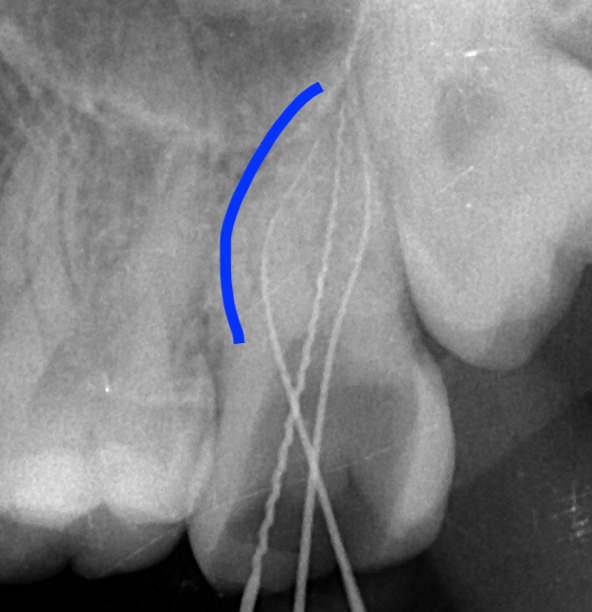

根管は細くて曲がっている場合も多々あります。その場合、細い

針のような器具を慎重に挿入して根管治療を行う必要があります。

画像のように根が曲がっている場合、慎重にファイルという

針を差し込んで根の先まで掃除しないといけません。